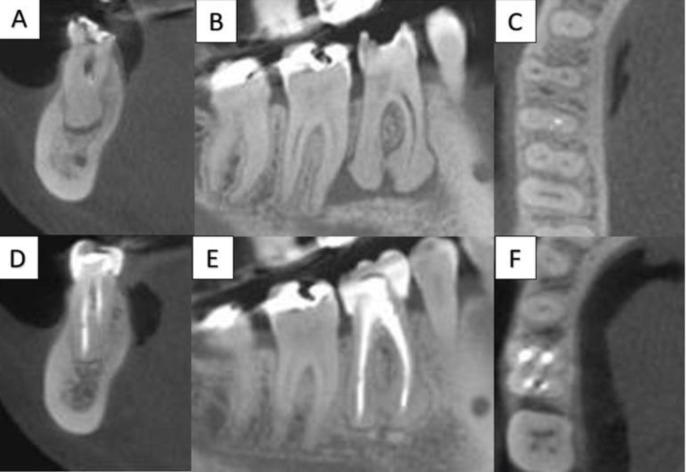

This case report describes the use of the guided endodontics for a non-surgical endodontic retreatment of the mandibular molar. A 38-year-old female reported apical swelling and localized pain on the tooth #30, exacerbated when chewing hard food. Periapical radiographic examination showed pulp canal obliteration in the apical third associated with extensive radiolucent area. Cone-beam computed tomography (CBCT) images were requested to support the diagnosis and enable preparation of a surgical guide, used to direct access to the canals that were obliterated and incompletely filled. The follow-up at 24 months radiographically showed completely healed apical area in the involved tooth. This non-surgical technique demonstrated efficacy in case resolution.

摘要

本病例报告描述了使用引导式牙髓治疗术对下颌磨牙进行非手术牙髓再治疗的情况。一名38岁女性报告称30号牙出现根尖肿胀和局部疼痛,咀嚼硬物时疼痛加剧。根尖X线片检查显示根尖三分之一处牙髓根管闭塞,并伴有广泛的透射区。请求进行锥形束计算机断层扫描(CBCT)成像以辅助诊断,并制作手术导板,用于引导进入闭塞和未完全充填的根管。术后24个月的X线片随访显示,患牙根尖区完全愈合。这种非手术技术在病例治疗中显示出了疗效。